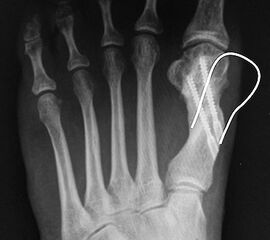

Abbildung 1

• Korrekturpotential größer als beim offenen Chevron, da die Gelenkkapsel als stabilisierendes Element erhalten bleibt und über eine trikortikale Osteosynthese mit zwei kanülierten Schrauben eine Verschiebung bis ca. 80% des Metatarsaledurchmessers möglich ist (Abb. 1).